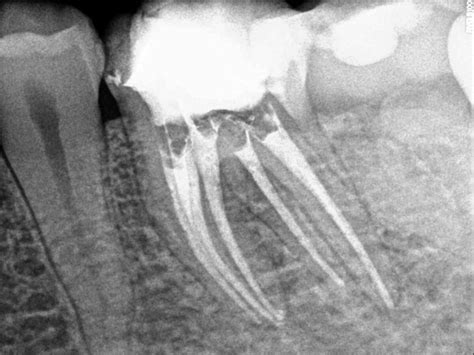

- Radiografía y Diagnóstico: El primer paso es realizar una radiografía que ayudará a valorar la posible afectación de la pulpa o del nervio del diente.

Para clasificar las endodoncias, es importante tener en cuenta que no todos los dientes tienen el mismo número de raíces ni de conductos radiculares. En las raíces de los dientes es donde se encuentran estos conductos radiculares.

- Multirradiculares o Polirradiculares: Molares superiores, que presentan tres raíces por pieza. En este grupo encontramos a los molares superiores que presentan 3 raíces por pieza.

En cada raíz del diente puede haber uno o más conductos que, en el caso de realizar una endodoncia, habrá que limpiar, desinfectar, rellenar y sellar convenientemente. Los conductos pulpares presentan diversas formas, ramificaciones y derivaciones que hacen más compleja la labor del especialista en endodoncia.